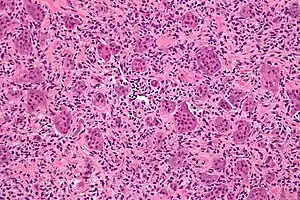

| Micrograph of a giant-cell tumor of bone showing the characteristic giant cells, H&E stain | |

The diagnosis of giant-cell tumors is based on biopsy findings. The key histomorphologic feature is, as the name of the entity suggests, (multinucleated) giant cells with up to a hundred nuclei that have prominent nucleoli. Surrounding mononuclear and small multinucleated cells have nuclei similar to those in the giant cells; this distinguishes the lesion from other osteogenic lesions which commonly have (benign) osteoclast-type giant cells. Soap-bubble appearance is a characteristic feature.